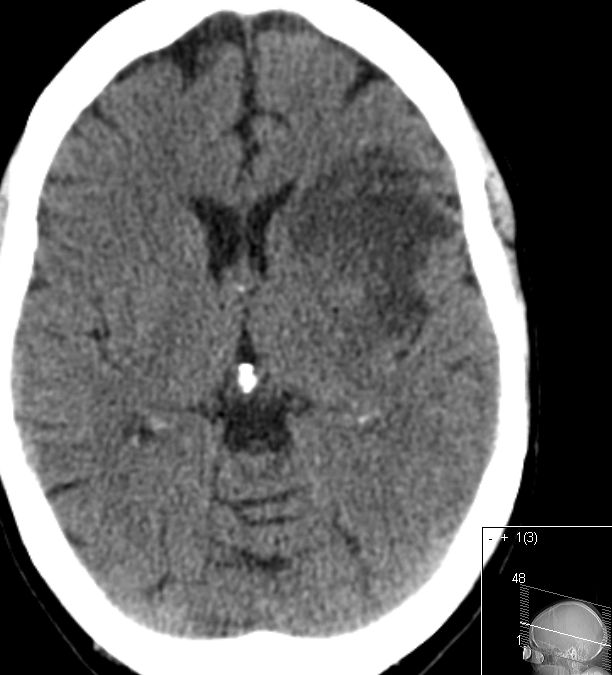

ACI-Verschluß 63-jährige Frau, die wegen TIA eingeliefert wurde. Daraus entwickelte sich eine komplette Halbseitensymptomatik. Das CT zeigt einen Abgangsverschluss der linke ACI.

CT-Angio

Gut markierter Media-Infarkt